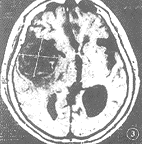

2.2.2 MR征象:病灶呈圆形或类圆形,5例中4例边界清晰可辨,在T1WI及T2WI上病灶内均有不同大小的“流空”现象所致的MR信号缺失区,呈黑色阴影,T2WI上黑色区域大于T1WI所显示的范围,周边呈混杂信号,混杂信号的大部分在T1WI上较脑灰质信号稍高,在T2WI上稍低于脑灰质。增强MR扫描可见部分混杂信号有轻度强化现象,1例见瘤壁明显强化(图3~6)。

图3 右侧大脑中动脉巨大动脉瘤伴血栓形成。横断面SE序列T1WI上示右外侧裂区巨大占位性病变,大小4.2 cm×4.33 cm,内有“流空”信号及不规则混杂信号

图4 图3病例T2WI示大片“流空”信号